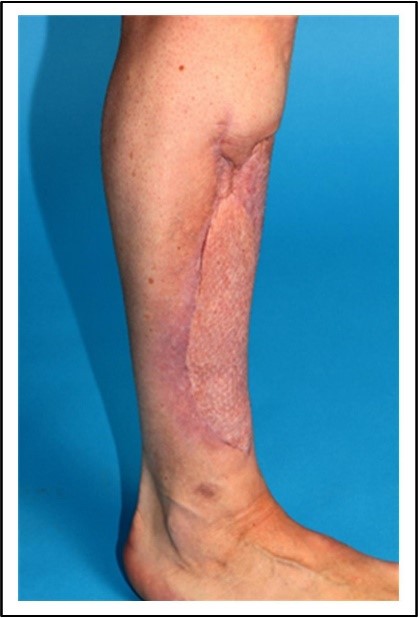

Abb. 1: Deckung von Hautdefekten nach Entfernung großer Weichgewebstumoren, welche so dicht an die Haut heran gewachsen waren, dass diese nicht erhalten werden konnte. Dafür wurde eine Spalthautplastik verwendet, die dem Patient von einer gesunden Stelle entnommen und so aufgearbeitet wurde, dass diese den Hautdefekt bedeckt.